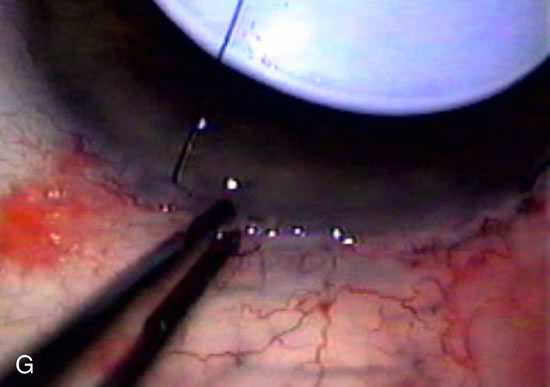

Fig. 2. Wound modulation and revision. A. MMC decreases the likelihood of bleb failure in high-risk eyes undergoing combined cataract and glaucoma surgery. Overusage of this potent cytotoxic drug should be avoided owing to a myriad of problems related to the formation of an avascular bleb. B. Office-based laser revision of the operative wound allows for increased postoperative flexibility with less complications. The correct number and tension of scleral flap sutures allows the surgeon to strive for a safe immediate postoperative IOP range. When fibrosis occurs at approximately 1 week, suturelysis or release of sutures increases filtration while avoiding unwanted hypotony.

In years past, patients with both cataract and glaucoma frequently provided overwhelming surgical challenges for the ophthalmologist. The ability to carry out phacoemulsification through a 3.2-mm corneal incision along with inserting a foldable IOL is a vast improvement over 11-mm incisions that were common a decade ago (Fig. 1). The anatomical and inflammatory changes to the eye are less with small incision techniques, improving the likelihood of success with concomitant glaucoma surgery. Pharmacologic inhibition of fibrosis along with postoperative wound revision increases the long-term success rate of filtration surgery when combined with lens extraction. (Fig. 2). The learning curve may be steep at times, but the blending of cataract and glaucoma surgical skills slowly falls into place as the surgeon constantly learns and upgrades his or her technique.